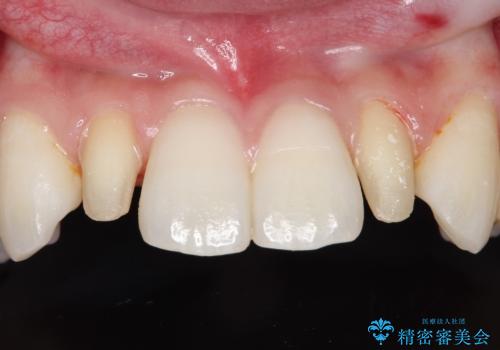

- 当院で矯正治療を行っており、上の前から2番目の歯の形も気になるので治したいと希望がありました。

矮小歯といわれる通常よりも小さい歯であったので、こちらにオールセラミッククラウンを装着して自然な歯の形にすることにしました。

上の前から2番目の歯を少量削らなければならないデメリットはありますが、クラウンの装着により自然な形へすることができました。